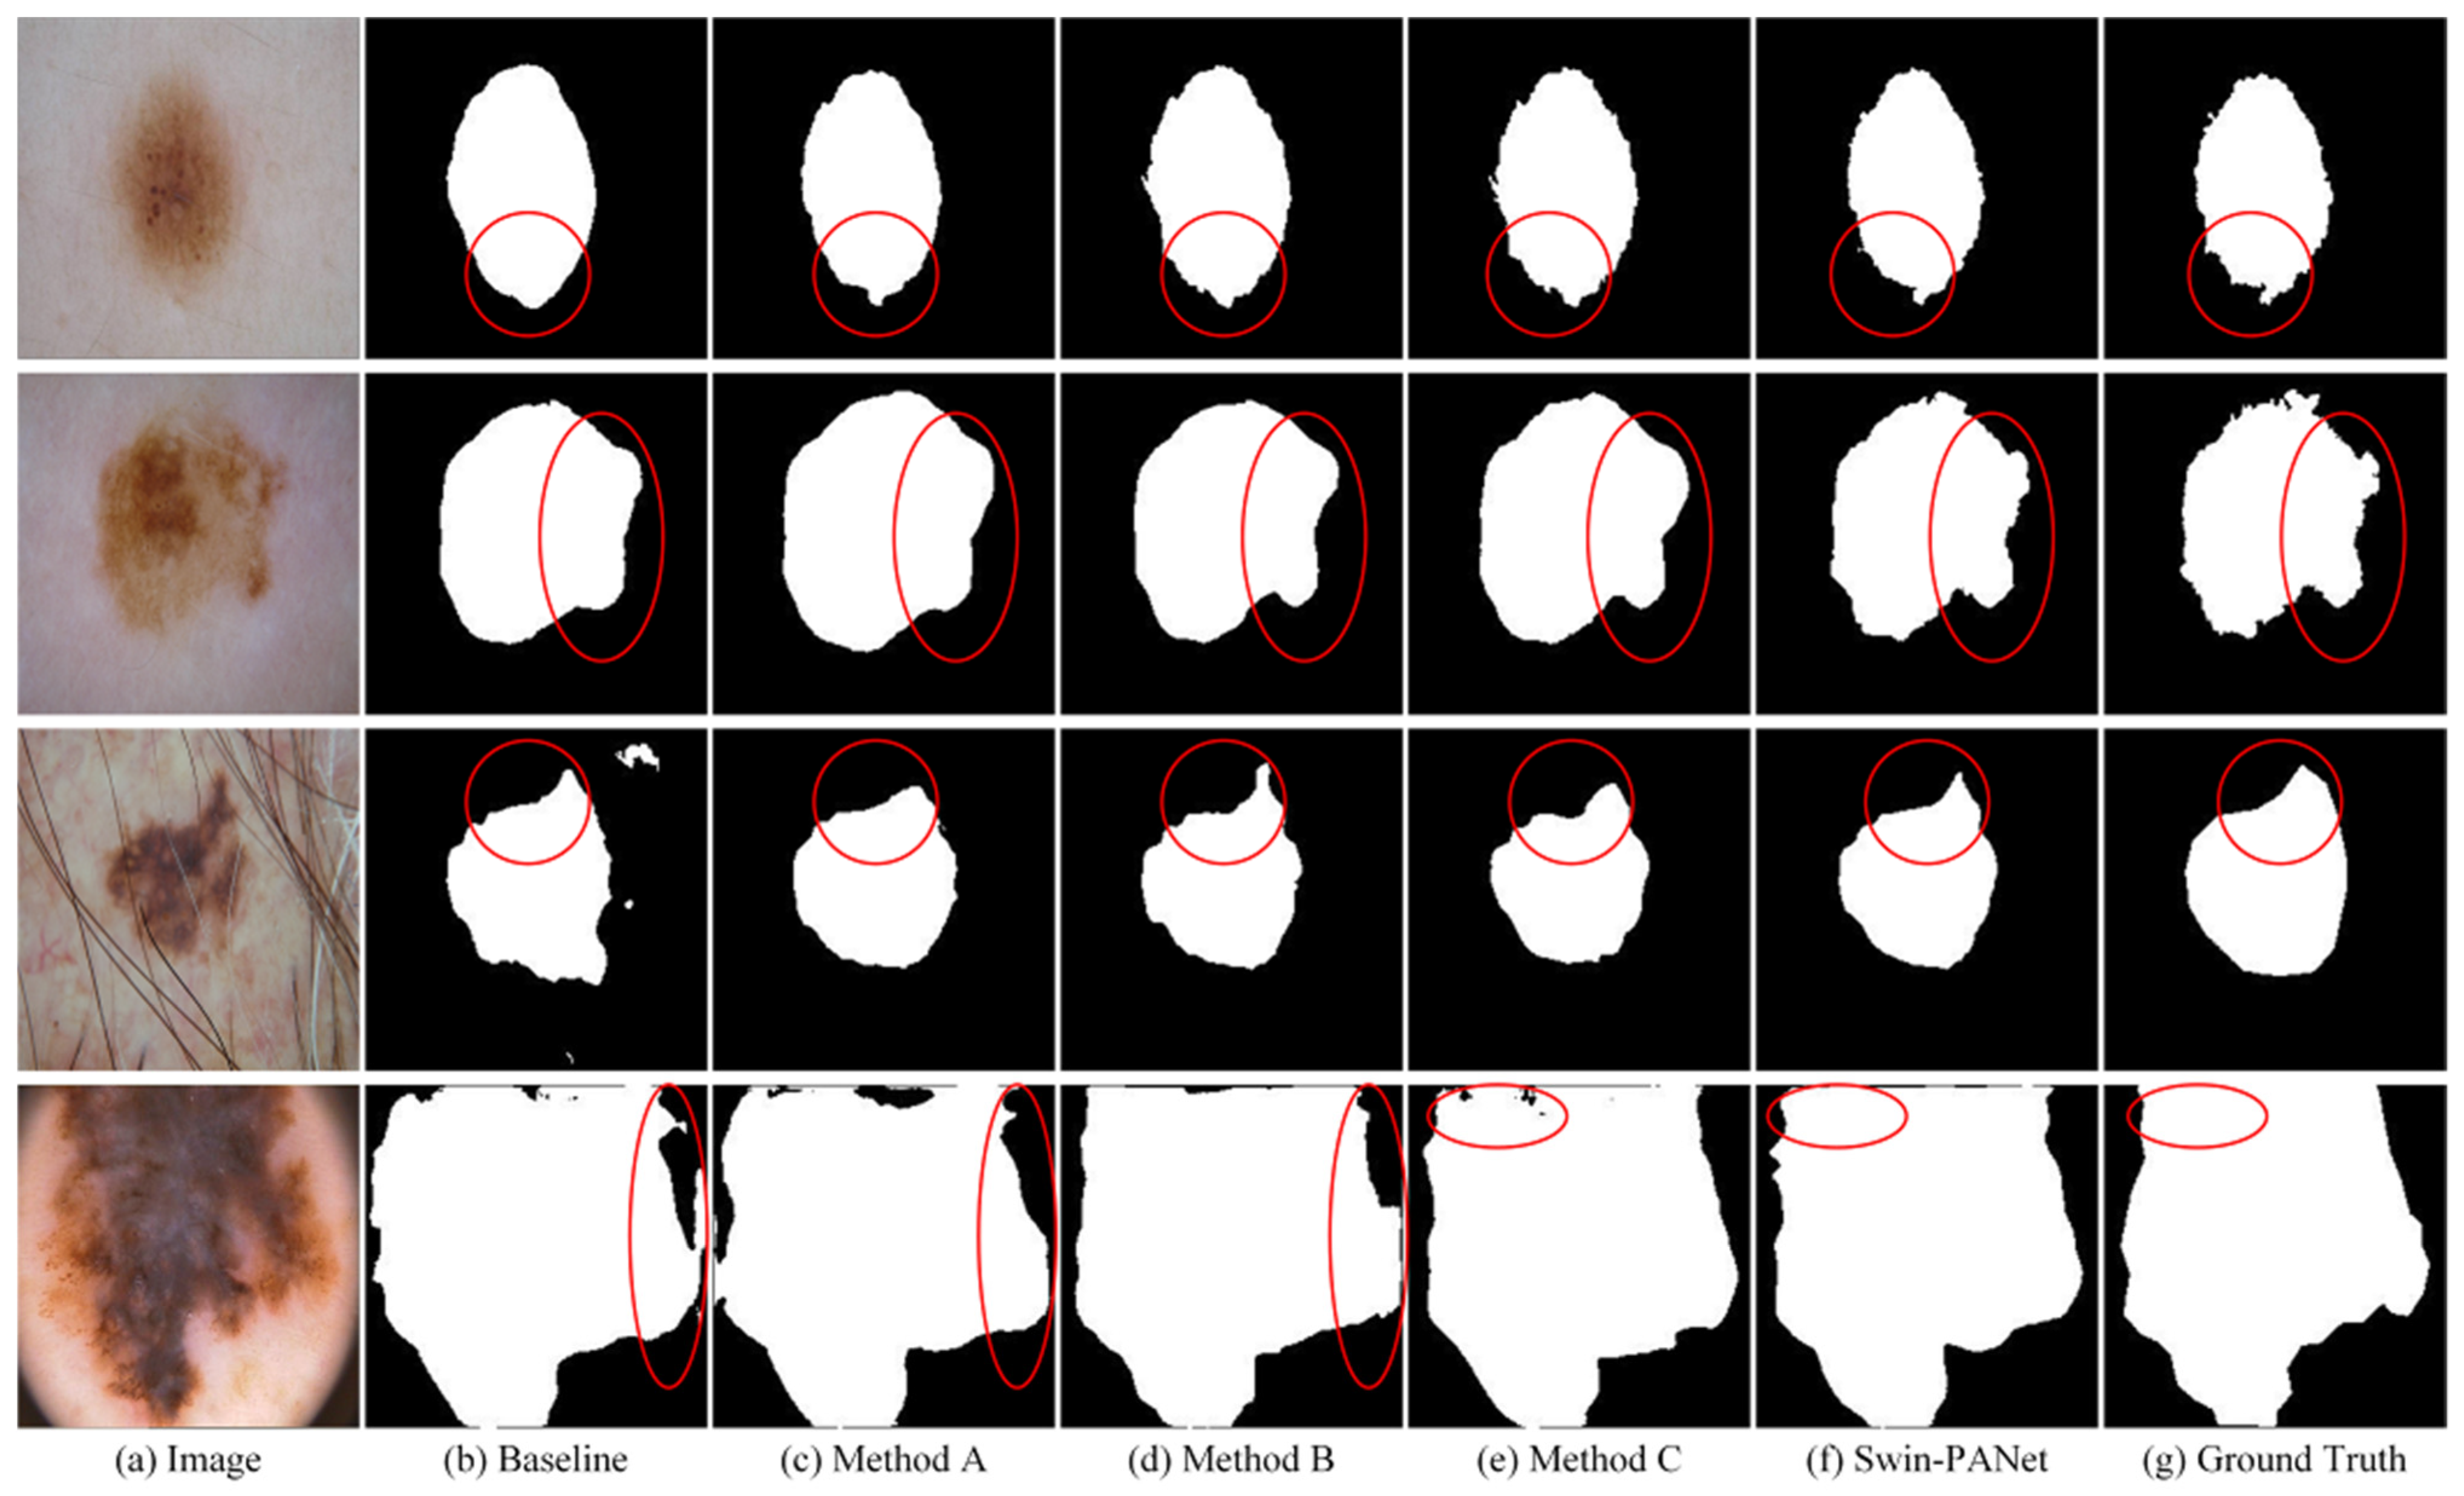

4.3. Ablation Studies

| Method | ISIC 2016 | |

|---|---|---|

| Dice (%) | IoU (%) | |

| Baseline (U-Net) | 86.82 | 78.23 |

| Baseline + Swin − Trans | 89.98 | 83.43 |

| Baseline + AGD | 89.79 | 82.81 |

| Baseline + AGD + EAB | 90.12 | 83.74 |

| Baseline + Swin − Trans + EAB | 89.56 | 82.50 |

| Baseline + Swin − Trans +AGD + EAB | 90.68 | 84.06 |